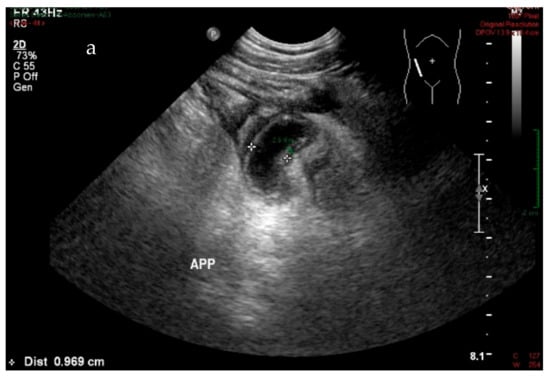

During this study, an accurate diagnosis was made using US when the diameter of the vermiform appendix was 7 mm or more, leading to a sensitivity of 74% and a PPV of 93.3% (See Figure 4a,b). The presence of free fluid also afforded a sensitivity of 53% and a PPV of 95% (See Figure 4c). The presence of free fluid is widely known as a secondary feature, and it could often be suggestive of an abdominal condition but not specific for appendicitis [26,27]. In this study, approximately 50% of cases presented free fluid showed an absence of a distinctly visualized appendix. Therefore, radiologists argue that the appendix must be seen to confirm the inflammation. Nevertheless, the visualization of the appendix can often be difficult. It has been found that repeating ultrasound examination for secondary features after a few hours is necessary. It significantly improved ultrasound sensitivity and patient’s management [28].

Figure 4.

Longitudinal (a) and transverse (b) real-time ultrasound scan of acute appendicitis with diameter > 7 mm (white measure) and wall thickness 2.6 mm (green measure) for 33-year-old male patient with pain in the right lower quadrant; transverse (c) real-time ultrasound scan for 34-year-old female patient with suspected appendicitis shows free fluid in the right lower quadrant.